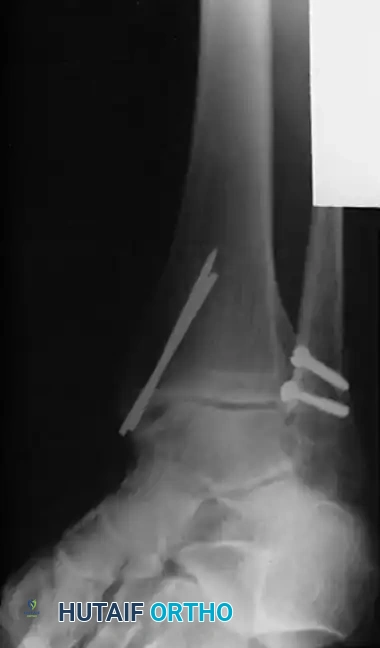

Surgical Sequence for Bimalleolar Fixation

- Lateral Side First: The fibula is typically addressed first to restore the length and rotation of the lateral column. This often indirectly reduces the talus and simplifies the medial reduction.

- Medial Side Second: Once the lateral mortise is established, the medial malleolus is directly reduced and fixed.

- Syndesmotic Evaluation: After bimalleolar fixation, the syndesmosis must be tested using the "Cotton test" (lateral traction on the fibula using a bone hook). If widening occurs, syndesmotic screws or flexible suture-button constructs are required.